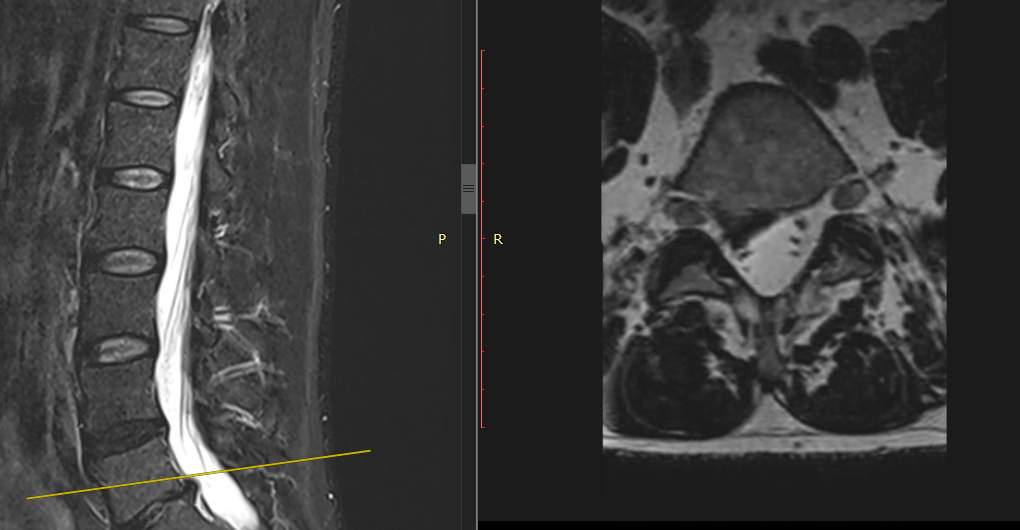

Un patient presente une douleur irradiant au pied droit : vous evoquez une sciatique, le trajet est posterieur, irradie à la plante du pied

Il s'agit d'une sciatique S1, faiblesse possible des abaisseurs Une. Infection peut se compliquer d'une souffrance sciatique, ou radiculaire, par le biais d'une épidurite. Les drapeaux rouges correspondent au syndrome de la queue de cheval à connaître Le signe de l'énergie se voit dans la cruralgie, l'abolition du rotulien dans la cruralgie l'abolition de l'achiléen dans la sciatique S1